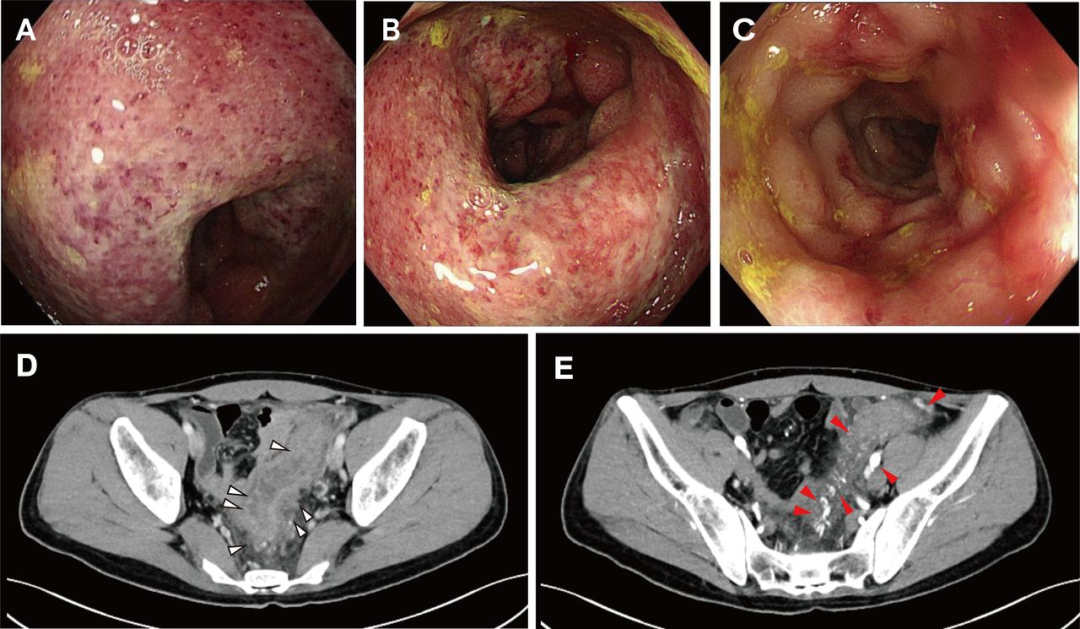

造血干细胞移植术后腹痛+黏液血便:这个极易误诊的肠道“隐形杀手”,千万别忽视!

病史摘要:患者为 36 岁男性,主诉持续性腹痛 5 个月,伴黏液血便 1 个月,后进展为不完全性肠梗阻。3 年前确诊急性 B 淋巴细胞白血病,并行异基因造血干细胞移植,移植后发生累及口腔及皮肤的急性移植物抗宿主病,使用环孢素、芦可替尼治疗至腹痛发作。 诊疗过程:实验室检查示 D - 二聚体及超敏 C 反应蛋白升高,其余正常。结肠镜见乙状结肠及直肠黏膜充血等改变,CT